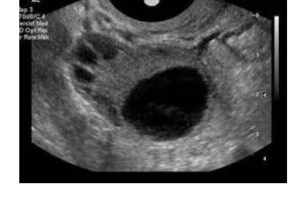

科学助孕:在必要情况下,可以通过卵泡监测(定期进行超声检查以观察卵泡的发育)和辅助生殖技术(如试管婴儿)等方法来提高怀孕的机会。